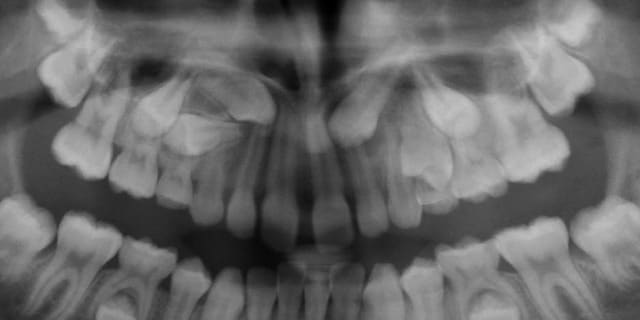

Jeune fille de 12 ans.

Que proposez-vous ?

Il n'y a aucun élément caché, cette panoramique se suffisait à elle-même pour montrer toute la problématique du cas en trois points :

- 13 incluse.

- 23 incluse.

- 14 "un peu" penchée, sa racine passe au dessus de l'apex de la 53 et vient titiller la couronne de la 13.